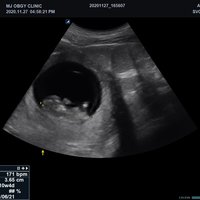

Volumen Konvex-Sonden

• SVC1-8H (1-8 MHz) für Ultraschalluntersuchungen in Bereichen Abdomen, Geburtshilfe, Gynäkologie, Urologie, Pädiatrie, EM